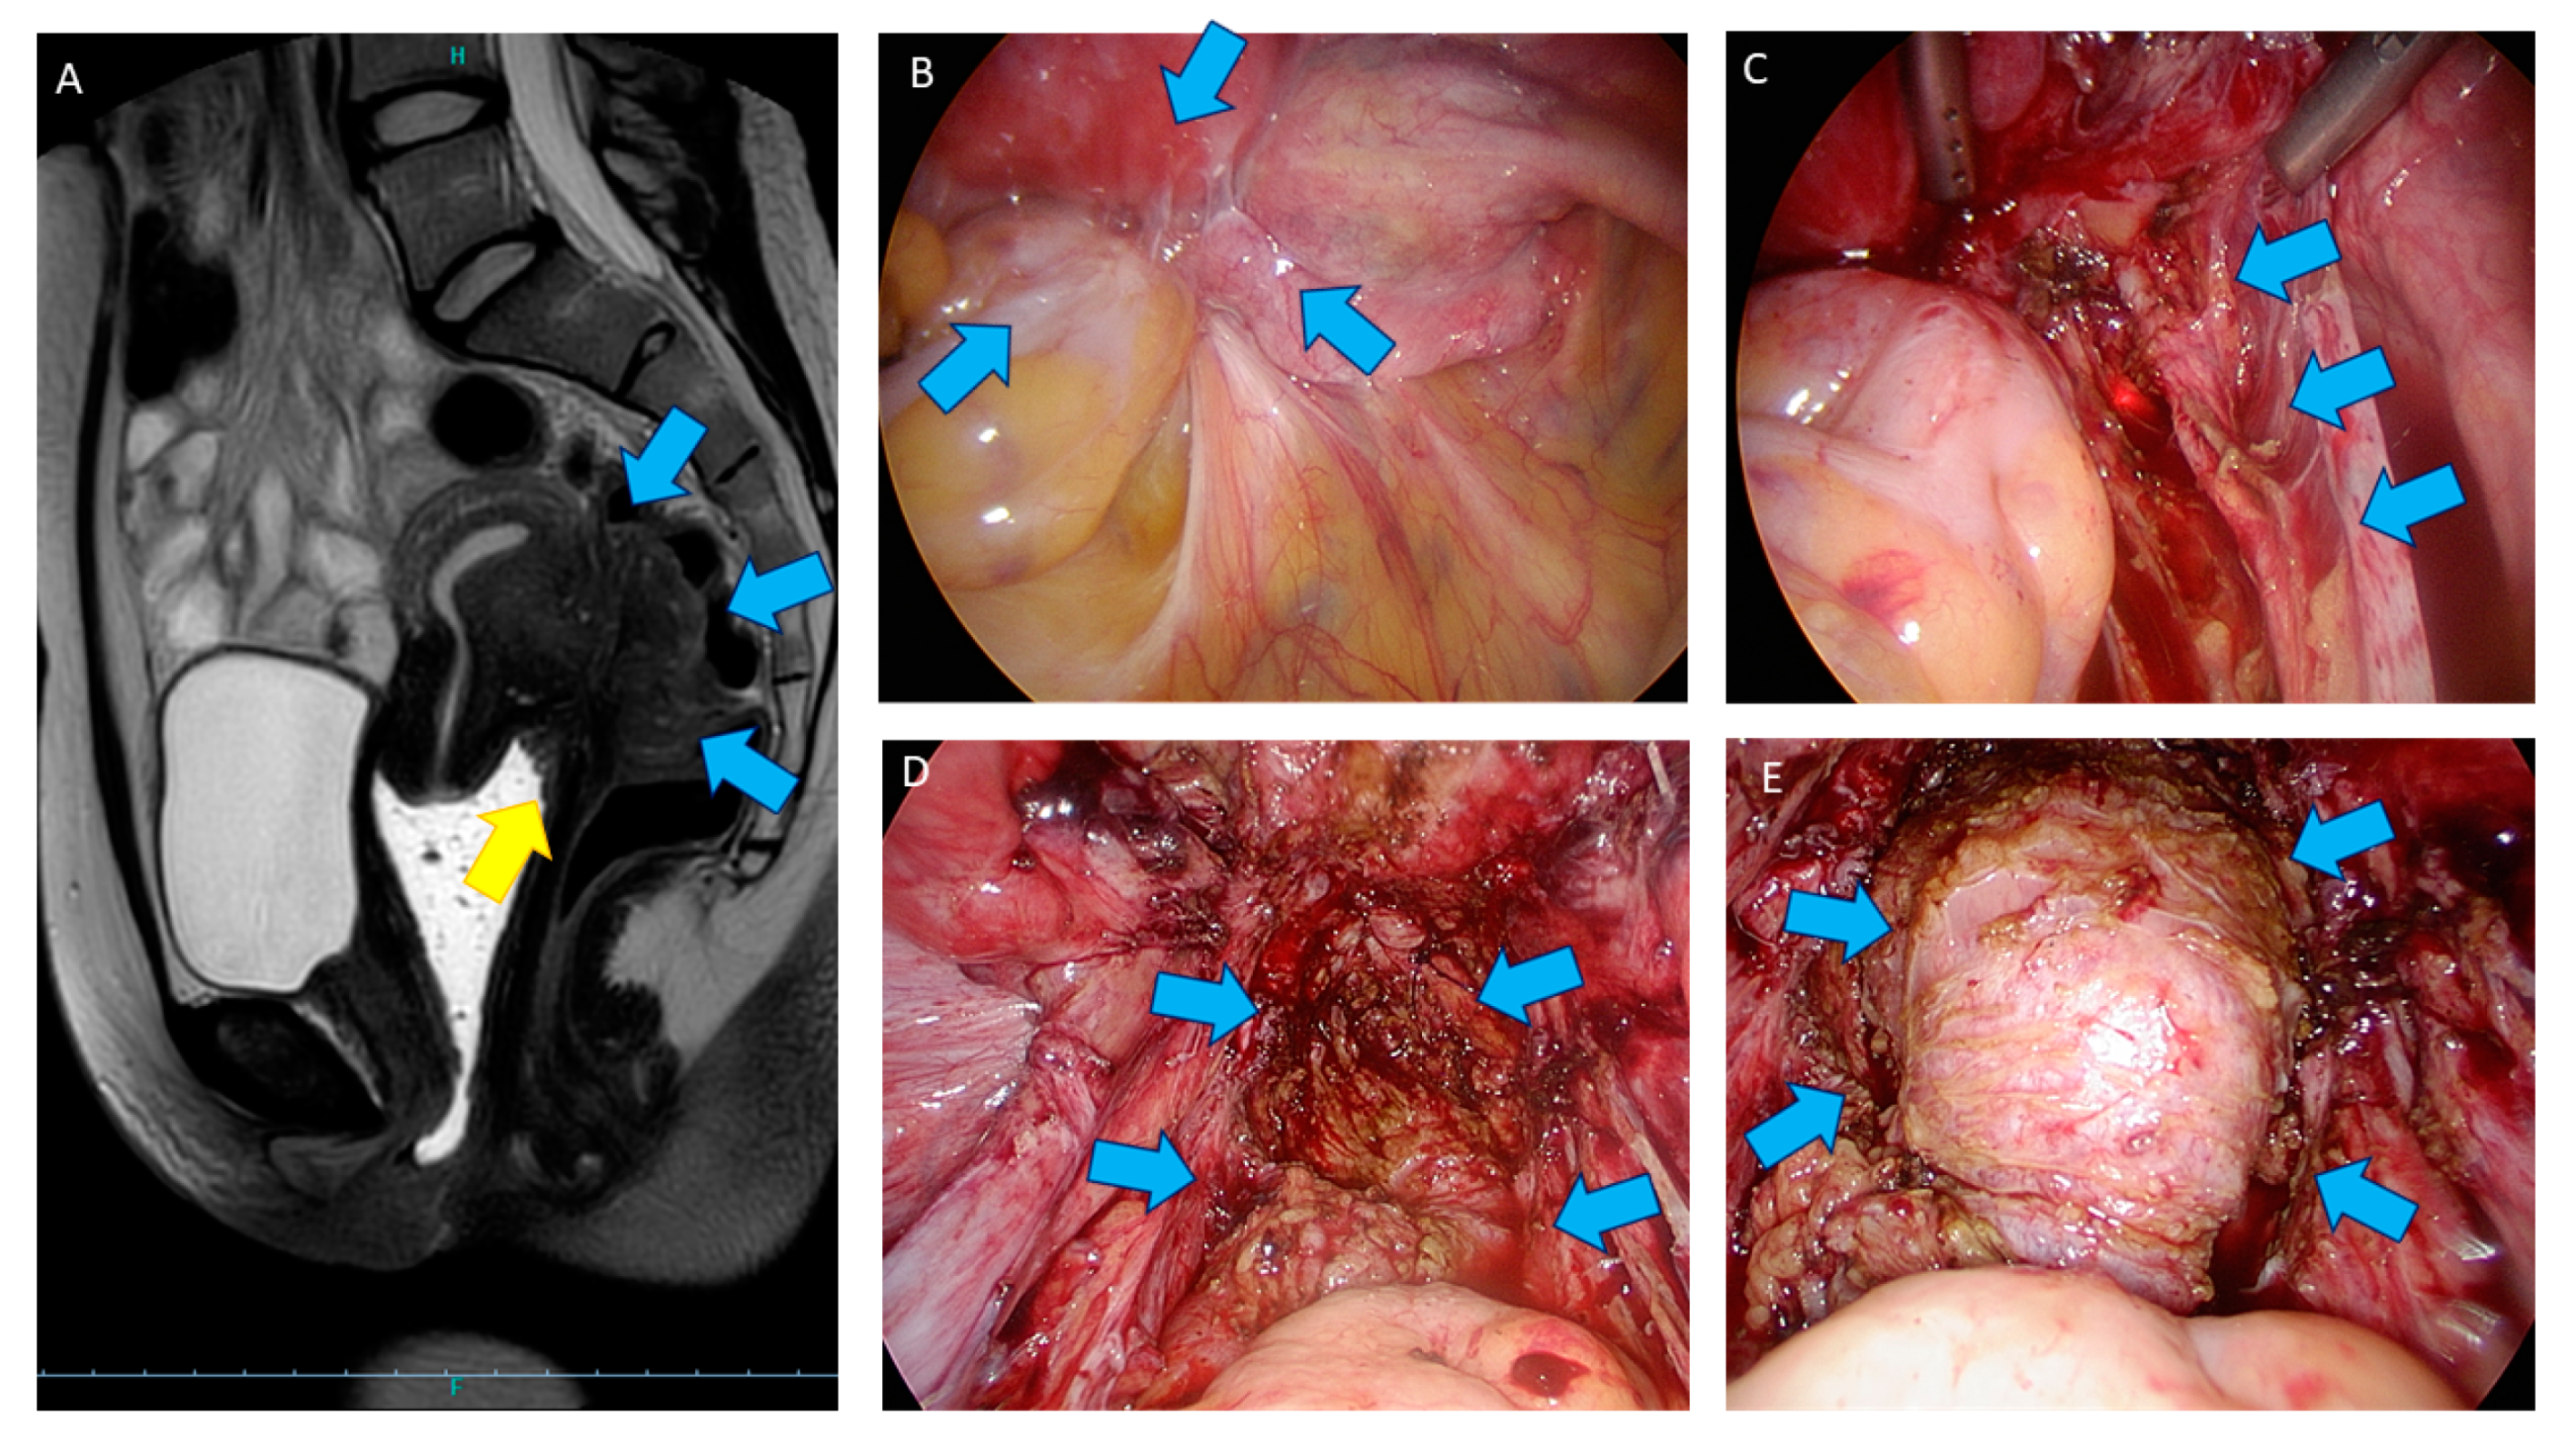

- Donnez, J.; Squifflet, J. Laparoscopic excision of deep endometriosis. Obstet. Gynecol. Clin. N. Am. 2004, 31, 567–580. [Google Scholar] [CrossRef]

- Donnez, O.; Roman, H. Choosing the right surgical technique for deep endometriosis: Shaving, disc excision, or bowel resection? Fertil. Steril. 2017, 108, 931–942. [Google Scholar] [CrossRef]

- Donnez, O.; Donnez, J. Deep endometriosis: The place of laparoscopic shaving. Best Pract. Res. Clin. Obstet. Gynaecol. 2021, 71, 100–113. [Google Scholar] [CrossRef]

- Donnez, J.; Squifflet, J. Complications, pregnancy and recurrence in a prospective series of 500 patients operated on by the shaving technique for deep rectovaginal endometriotic nodules. Hum. Reprod. 2010, 25, 1949–1958. [Google Scholar] [CrossRef]